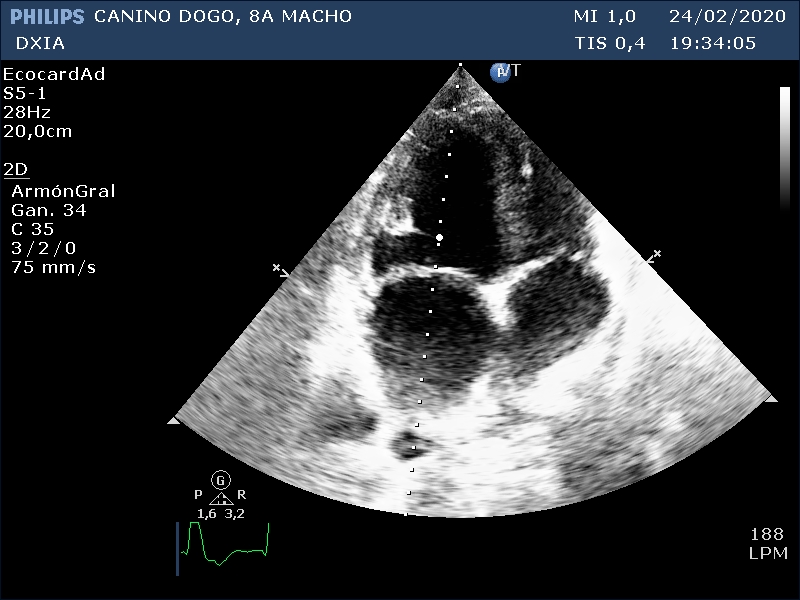

Se realiza estudio ecocardiográfico de urgencia, no siendo posible movilizarlo dado el tamaño del paciente y su estado, por lo que se realiza el estudio sin usar mesa exploratoria.

RESULTADOS ESTUDIO ECOCARDIOGRAFICO

Corte apical izquierdo 4 cámaras. Observamos aumento de cámaras cardiacas, cambios grosores paredes

Comentario respecto al estudio ecocardiográfico:

- Agrandamiento de cámaras derechas e izquierda con disminución grosores paredes cardíacas.

- Valva septal de la VM levemente engrosada con patrón nodular ¿degeneración?

- Varios indicadores de cambios compatibles con fenotipo de CMD.

- ECG fibrilación atrial.

CONCLUSIÓN:

Se recomendó hospitalización con tratamiento para estabilización y pruebas complementarias. No se realizó estudio abdominal. No se conoce evolución del caso.